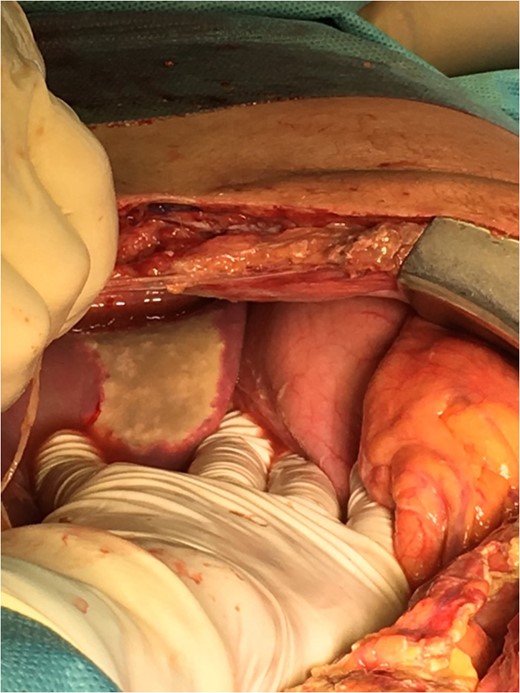

On the seventh postoperative day the patient's abdominal drain catheter presented enteric content, so he underwent a second explorative laparotomy. Two new perforations and multiple areas of patchy necrosis along the whole length of the small intestine were found (Fig. 1). All the lesions were suture repaired after debridement, and the patient was left with an open abdomen using a vacuum device, with a plan for re-laparotomy in 48 h (Fig. 2). After the second operation the patient started plasma exchanges for the treatment of PAN, along with IV cyclophosphamide 500 mg stat and IV methylprednisolone 1 gr daily for 3 days and then IV prednisone 60 mg daily.

On the third laparotomy, three new necrotic lesions, two on the small intestine and one on the cecum, were found and suture repaired (Fig. 3). A necrotic lesion on the left lobe of the liver was also found (Fig. 4). On the fourth laparotomy, segmental enterectomy with anastomosis and cholecystectomy were performed due to anastomotic leak and a gangrenous gallbladder.